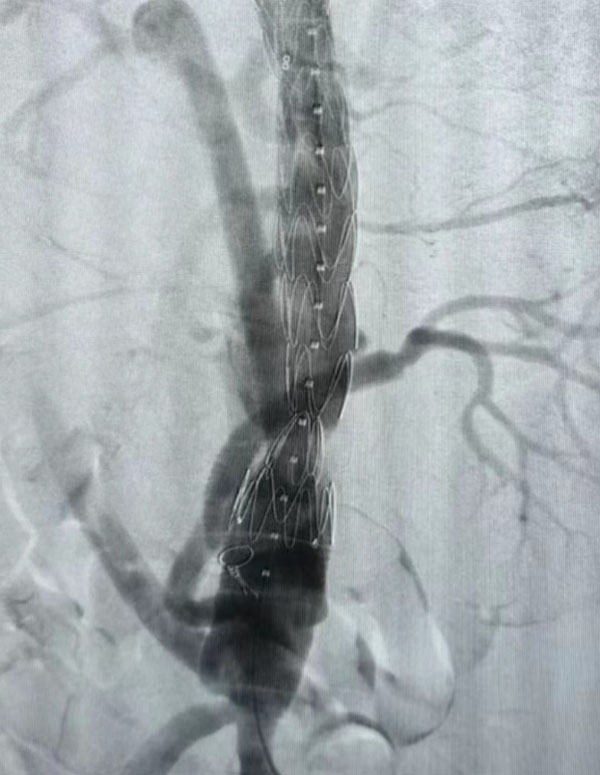

同期,另一臺“升主動脈置換+全主動脈弓置換+胸主動脈覆膜支架腔內隔絕術”正在開展,該病例為一名A型主動脈夾層患者。在主動脈弓及分支成功游離且心臟停跳后,心外科負責人趙永波“轉場”為患者完成了血管置換,心臟復跳成功,止血徹底。隨后,談凌凌主治醫師、侯五輝主治醫師為患者進行胸主動脈腔內修復。下午2點左右,兩臺手術成功結束。通過現場視頻直播,在手術同時,手術人員與大會現場的專家們就影像評估、手術策略、手術器械的選擇及操作技巧等多個環節進行了互動討論,學術氣氛熱烈,大會主席及與會代表給予我院高度評價。緊接著,手術團隊又為一名79歲腹主動脈瘤患者進行了腹主動脈腔內修復手術,效果良好,同樣受到與會專家的好評。

全主動脈弓置換